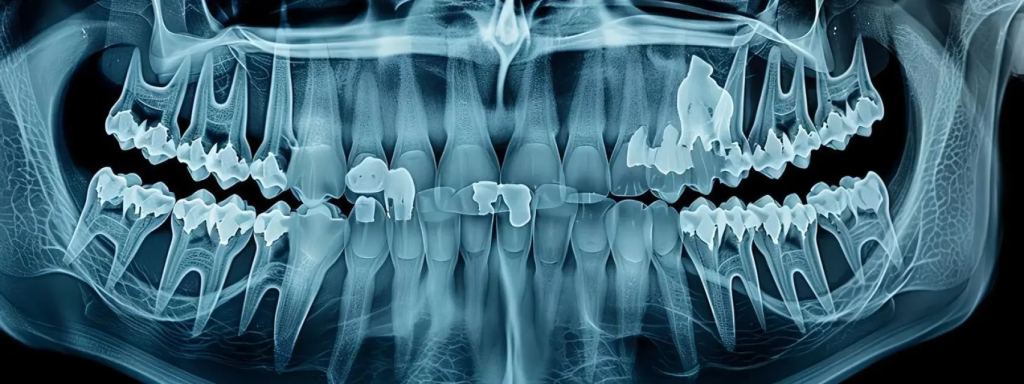

- Cuando los investigadores comenzaron a examinar el cráneo, notaron algo inusual en la mandíbula. Fue entonces cuando la Momia De Siberia De 2.500 Años Muestra Evidencia De Una Antigua Cirugía De Mandíbula empezó a revelar una historia médica inesperada. El hueso presentaba cortes precisos que no podían explicarse por causas naturales. Gracias a la tecnología moderna, como escáneres tridimensionales y tomografías computarizadas, los científicos pudieron estudiar el cráneo sin dañar los restos. Estas herramientas permitieron confirmar que las marcas eran resultado de una intervención humana.

- El análisis detallado del hueso mandibular reveló signos claros de manipulación quirúrgica. Los científicos observaron cortes limpios y modificaciones en el hueso que sugieren el uso de herramientas afiladas. Este tipo de marcas no puede ser causado por animales, erosión natural o procesos de descomposición.

- La evidencia indica que alguien realizó un procedimiento médico para tratar una lesión grave. Los investigadores creen que la cirugía pudo haberse realizado para corregir una fractura causada por una caída, un accidente o incluso un enfrentamiento violento.

- Lo más sorprendente es que el hueso muestra signos de regeneración. Esto significa que el paciente sobrevivió después de la cirugía. Este detalle demuestra que la Momia De Siberia De 2.500 Años Muestra Evidencia De Una Antigua Cirugía De Mandíbula realizada con suficiente precisión para permitir que el cuerpo iniciara el proceso de curación.

- Las tomografías computarizadas permiten analizar estructuras internas sin dañar los restos antiguos. Los escáneres 3D permiten crear modelos digitales del esqueleto que los investigadores pueden estudiar con gran precisión.

Los investigadores utilizaron tomografías computarizadas y escáneres 3D para analizar el cráneo y detectar marcas quirúrgicas.